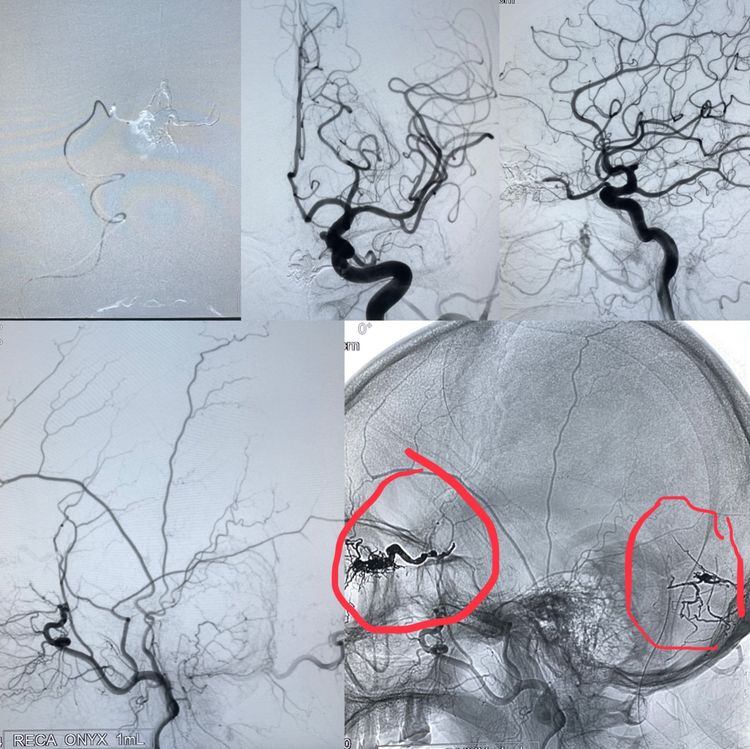

我们首先经眼动脉注胶治愈了前颅窝的硬脑膜动静脉瘘,然后又经过脑膜动脉分支治愈了后颅窝的动静脉瘘。

图上标注的就是铸型的胶了。